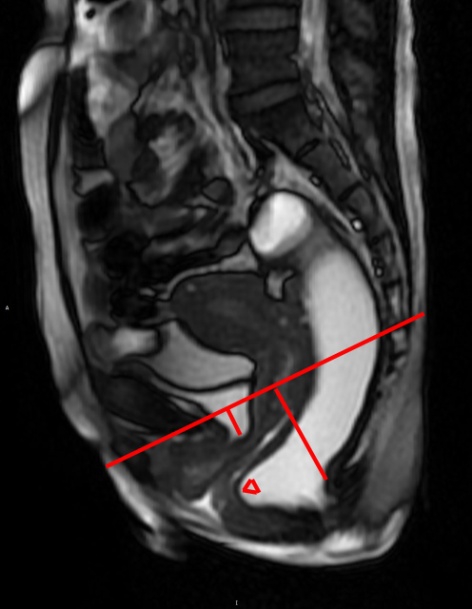

图1:检查结果

女性,40岁,分娩史,便秘5年余,并尿失禁。MRD扫描排便相所示肛管下降35mm、膀胱下降9mm、直肠中度前突16mm(△)。